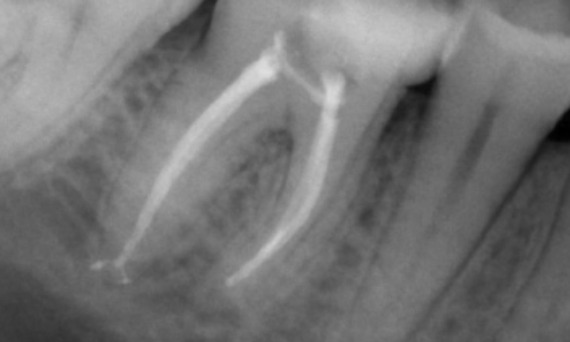

Before: Periapical radiolucency associated primarily with the distal root and loss of lamina dura on the mesial root.

After: TruNatomy was chosen in this case to allow a caries leveraged approach and a focus on pericervical dentin preservation especially on the mesial aspect where the tooth had a more minimal restoration.

"A patient and process centered success." - Dr. Cowie